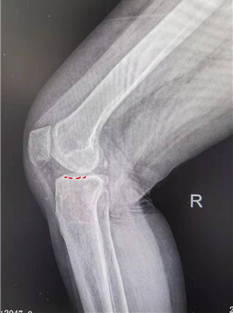

田女士手术前的膝关节X线片,正位可见内侧间室骨对骨(左,红色实线),侧位可见平台前内侧骨磨损(右,红色虚线)